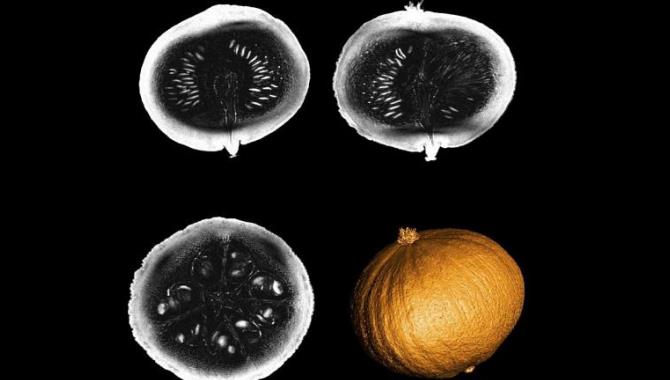

Nörolojik hastalıkların teşhisinde derin etkileri olabilecek dünyanın en güçlü MRI tarayıcısı, ilk önce bir balkabağı üzerinde test edildi ve ilk görüntüler yayınladı.

Neden insan beyni değil de balkabağı ?

Lerman, "Kabak, beyinle aynı çapa, tahıllar ve lifli kısımlara sahip ilginç, karmaşık bir iç yapıya sahip - ve bir de testi yaptığımızda mevsimiydi." diyor.